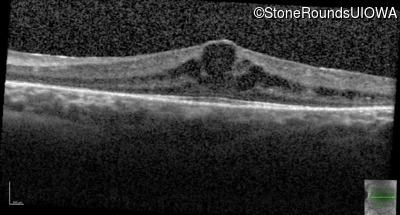

Age at visit: 7 years

This 7 year old girl has had very poor vision in dim light and slightly subnormal acuity her entire life.

Age at visit: 7 years (Visit 2)

Age at visit: 8 years

Age at visit: 9 years

Age at visit: 10 years

Age at visit: 12 years

Age at visit: 13 years

Age at visit: 14 years

Age at visit: 15 years

Age at visit: 16 years

Age at visit: 17 years

Age at visit: 19 years

Age at visit: 21 years